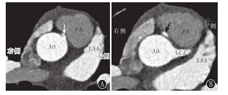

MSCT较高的空间分辨率和时间分辨率(<500 ms)能显示冠状动脉开口的位置及走行,以及其继发改变及伴发畸形(图4),所以MSCT在儿童冠状动脉疾病的诊断中得到较好应用。但其不足之处在于,MSCT很难对冠状动脉是否合并主动脉壁内走行做出准确诊断。

注:AO:主动脉;PA:肺动脉;LAA:左心耳;LCA:左冠状动脉;A:可见右冠状动脉起源于左冠窦,箭头所示为右冠状动脉;B:左冠状动脉起源正常,箭头所示为位于主动脉与肺动脉之间的右冠状动脉 AO:aorta;PA:pulmonary artery;LAA:left atrial appendage;LCA:left coronary artery;A:anomalous origin of right coronary artery from the left sinus,arrow indicates right coronary artery;B:the origin of left coronary artery is normal,arrow demonstrates the anomalous right coronary artery coursing between the aorta and pulmonary artery